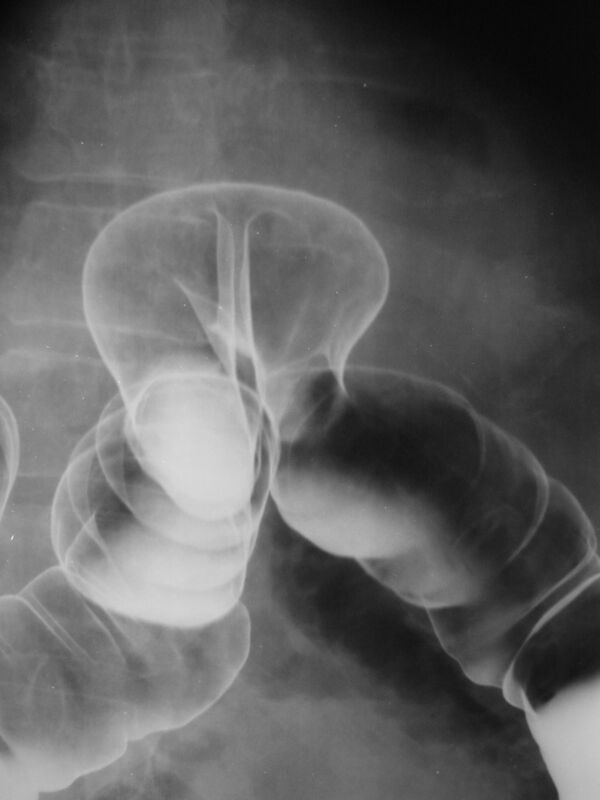

В зависимости от метода исследования, контрастные вещества отличаются по своему составу и способу введения. История медицинских контрастных веществ начинается в 1931 году с создания первых поглощающих рентгеновские лучи и безвредных для организма препаратов. Наиболее распространённым в классической рентгенологии рентгеноконтрастным веществом является сульфат бария. Главным недостатком этого вещества является его нерастворимость в воде, в связи с чем невозможно использовать сульфат бария там, где есть угроза попадания его за пределы полого органа (в брюшную полость, в кровоток и т. д.). В качестве естественного контрастного вещества используется атмосферный воздух, который, в отличие от сульфата бария, является рентгенонегативным (поглощает рентгеновское излучение слабее тканей тела, создавая рентгенологический эффект «просветления»). Такой способ контрастирования называется пневмографией. Для этой цели может быть использован любой газ. Так, например, для двойного контрастирования желудка больному даётся сода, и образовавшийся углекислый газ раздувает желудок, в который предварительно был введён сульфат бария — это позволяет осмотреть рельеф слизистой и состояние его стенок. В середине 80-х годов XX века были созданы контрастные препараты для МРТ и КТ.

Для исследования органов желудочно-кишечного тракта применяются как взвеси нерастворимых в воде веществ (сульфат бария), так и йодсодержащие вещества. Нерастворимые контрастные вещества в целом более безопасные, т.к практически не взаимодействуют с тканями организма. Однако, в некоторых случаях предпочтение отдаётся водорастворимым контрастным веществам — например, при подозрении на перфорацию полого органа или кишечную непроходимость.